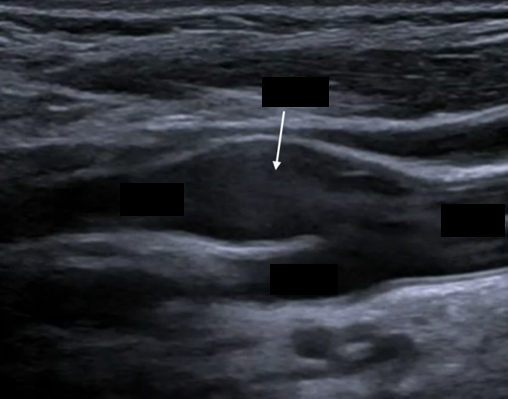

In this picture, what is the arrow pointing at?

Bulb